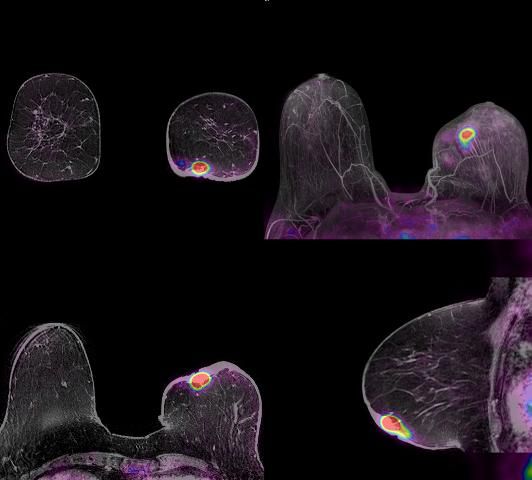

Five years after the first reports linking gadolinium-based MRI contrast agents to nephrogenic system fibrosis (NSF), separate presentations of post-marketing data from manufacturers and an independent prospective study supported by agencies in France have validated the low-risk status of the contrast agent Dotarem (Gd-DOTA).